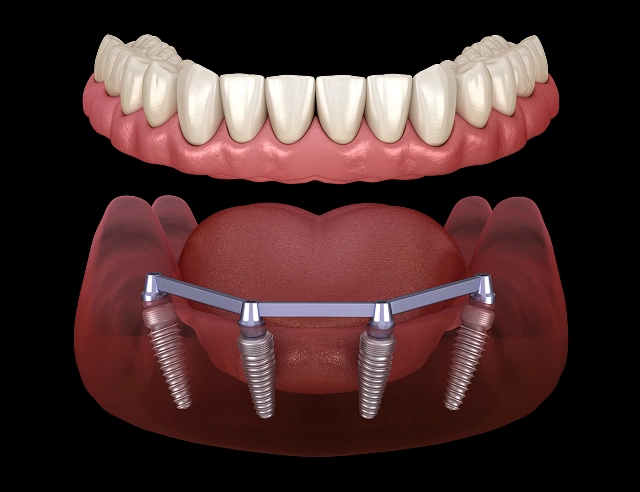

All-On-4

“Teeth in a Day”

All-on-4 Cost

$14,999

Starting as low as: $350/moSingle Arch

Upper or Lower